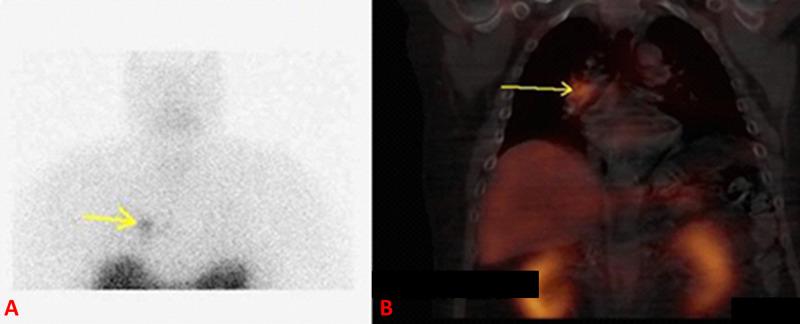

Ectopic Cushing's syndrome is a severe form of Cushing disease. Treatment usually involves the resection of the adrenocorticotropic hormone producing tumor. In certain cases, bilateral adrenalectomy is carried out as a final resort in treatment. We present a patient who had a lung carcinoid tumor, which was producing adrenocorticotropic hormone and causing ectopic Cushing's syndrome. Lung wedge resection failed to normalize cortisol level, and he had bilateral adrenalectomy. Ten years later, he had a recurrence of Cushing's disease due to lymph node metastasis of his carcinoid tumor.

异位库欣综合征是库欣病的一种严重形式。治疗通常包括切除产生促肾上腺皮质激素的肿瘤。在某些情况下,双侧肾上腺切除术作为治疗的最后手段实施。我们报告一名患有肺类癌肿瘤的患者,该肿瘤产生促肾上腺皮质激素并导致异位库欣综合征。肺楔形切除术未能使皮质醇水平恢复正常,于是他接受了双侧肾上腺切除术。十年后,由于类癌肿瘤的淋巴结转移,他的库欣病复发。